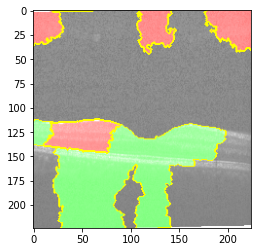

Explanation D

Explanation D

Explanation D

Explanation D

Fig 6, 7, 8 and 9 depicts the visualization of correct predictions by our proposed CNN model where fig 6 is class CNV, fig 8 is class DME, fig 7 is DRUSEN and finally, fig 9 is NORMAL. Here the first photo in every class is the original image. The LIME map of our suggested model’s prediction is shown in image B whereas in image C the positive region is highlighted in specific sections on the original image. For Image D we have increased the number of features from 5 to 10 thus more regions have been predicted as the positive region which is highlighted in green. After increasing the features from 5 to 10, some of the regions are predicted wrongly. The red regions represent the output of incorrect prediction. The following image represents the Grad-CAM heatmap highlighting the regions with our model’s prediction.